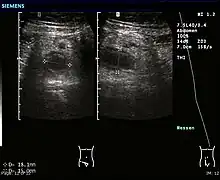

Ultrasound

Abdominal ultrasonography, preferably with doppler sonography, is useful to detect appendicitis, especially in children. Ultrasound can show the free fluid collection in the right iliac fossa, along with a visible appendix with increased blood flow when using color Doppler, and noncompressibility of the appendix, as it is essentially walled-off abscess. Other secondary sonographic signs of acute appendicitis include the presence of echogenic mesenteric fat surrounding the appendix and the acoustic shadowing of an appendicolith.[47] In some cases (approximately 5%),[48] ultrasonography of the iliac fossa does not reveal any abnormalities despite the presence of appendicitis. This false-negative finding is especially true of early appendicitis before the appendix has become significantly distended. Also, false-negative findings are more common in adults where larger amounts of fat and bowel gas make visualizing the appendix technically difficult. Despite these limitations, sonographic imaging with experienced hands can often distinguish between appendicitis and other diseases with similar symptoms. Some of these conditions include inflammation of lymph nodes near the appendix or pain originating from other pelvic organs such as the ovaries or Fallopian tubes. Ultrasounds may be either done by the radiology department or by the emergency physician.[49]